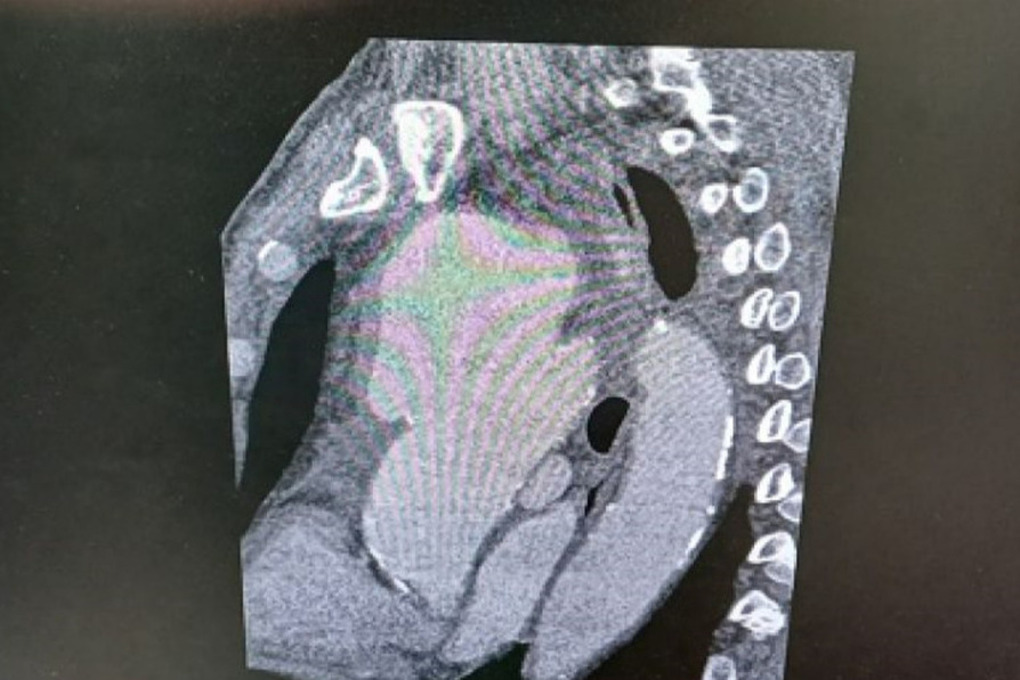

Фото: пресс-служба министерства здравоохранения Рязанской области

Дополнительные исследования подтвердили наличие гигантской аневризмы размером 9 на 9 сантиметров, которая сдавливала соседние органы и ткани. Как отметил заведующий отделением №5 Рязанского кардиодиспансера Сергей Загородный, такие случаи крайне редки, и разрыв аневризмы может привести к летальному исходу.